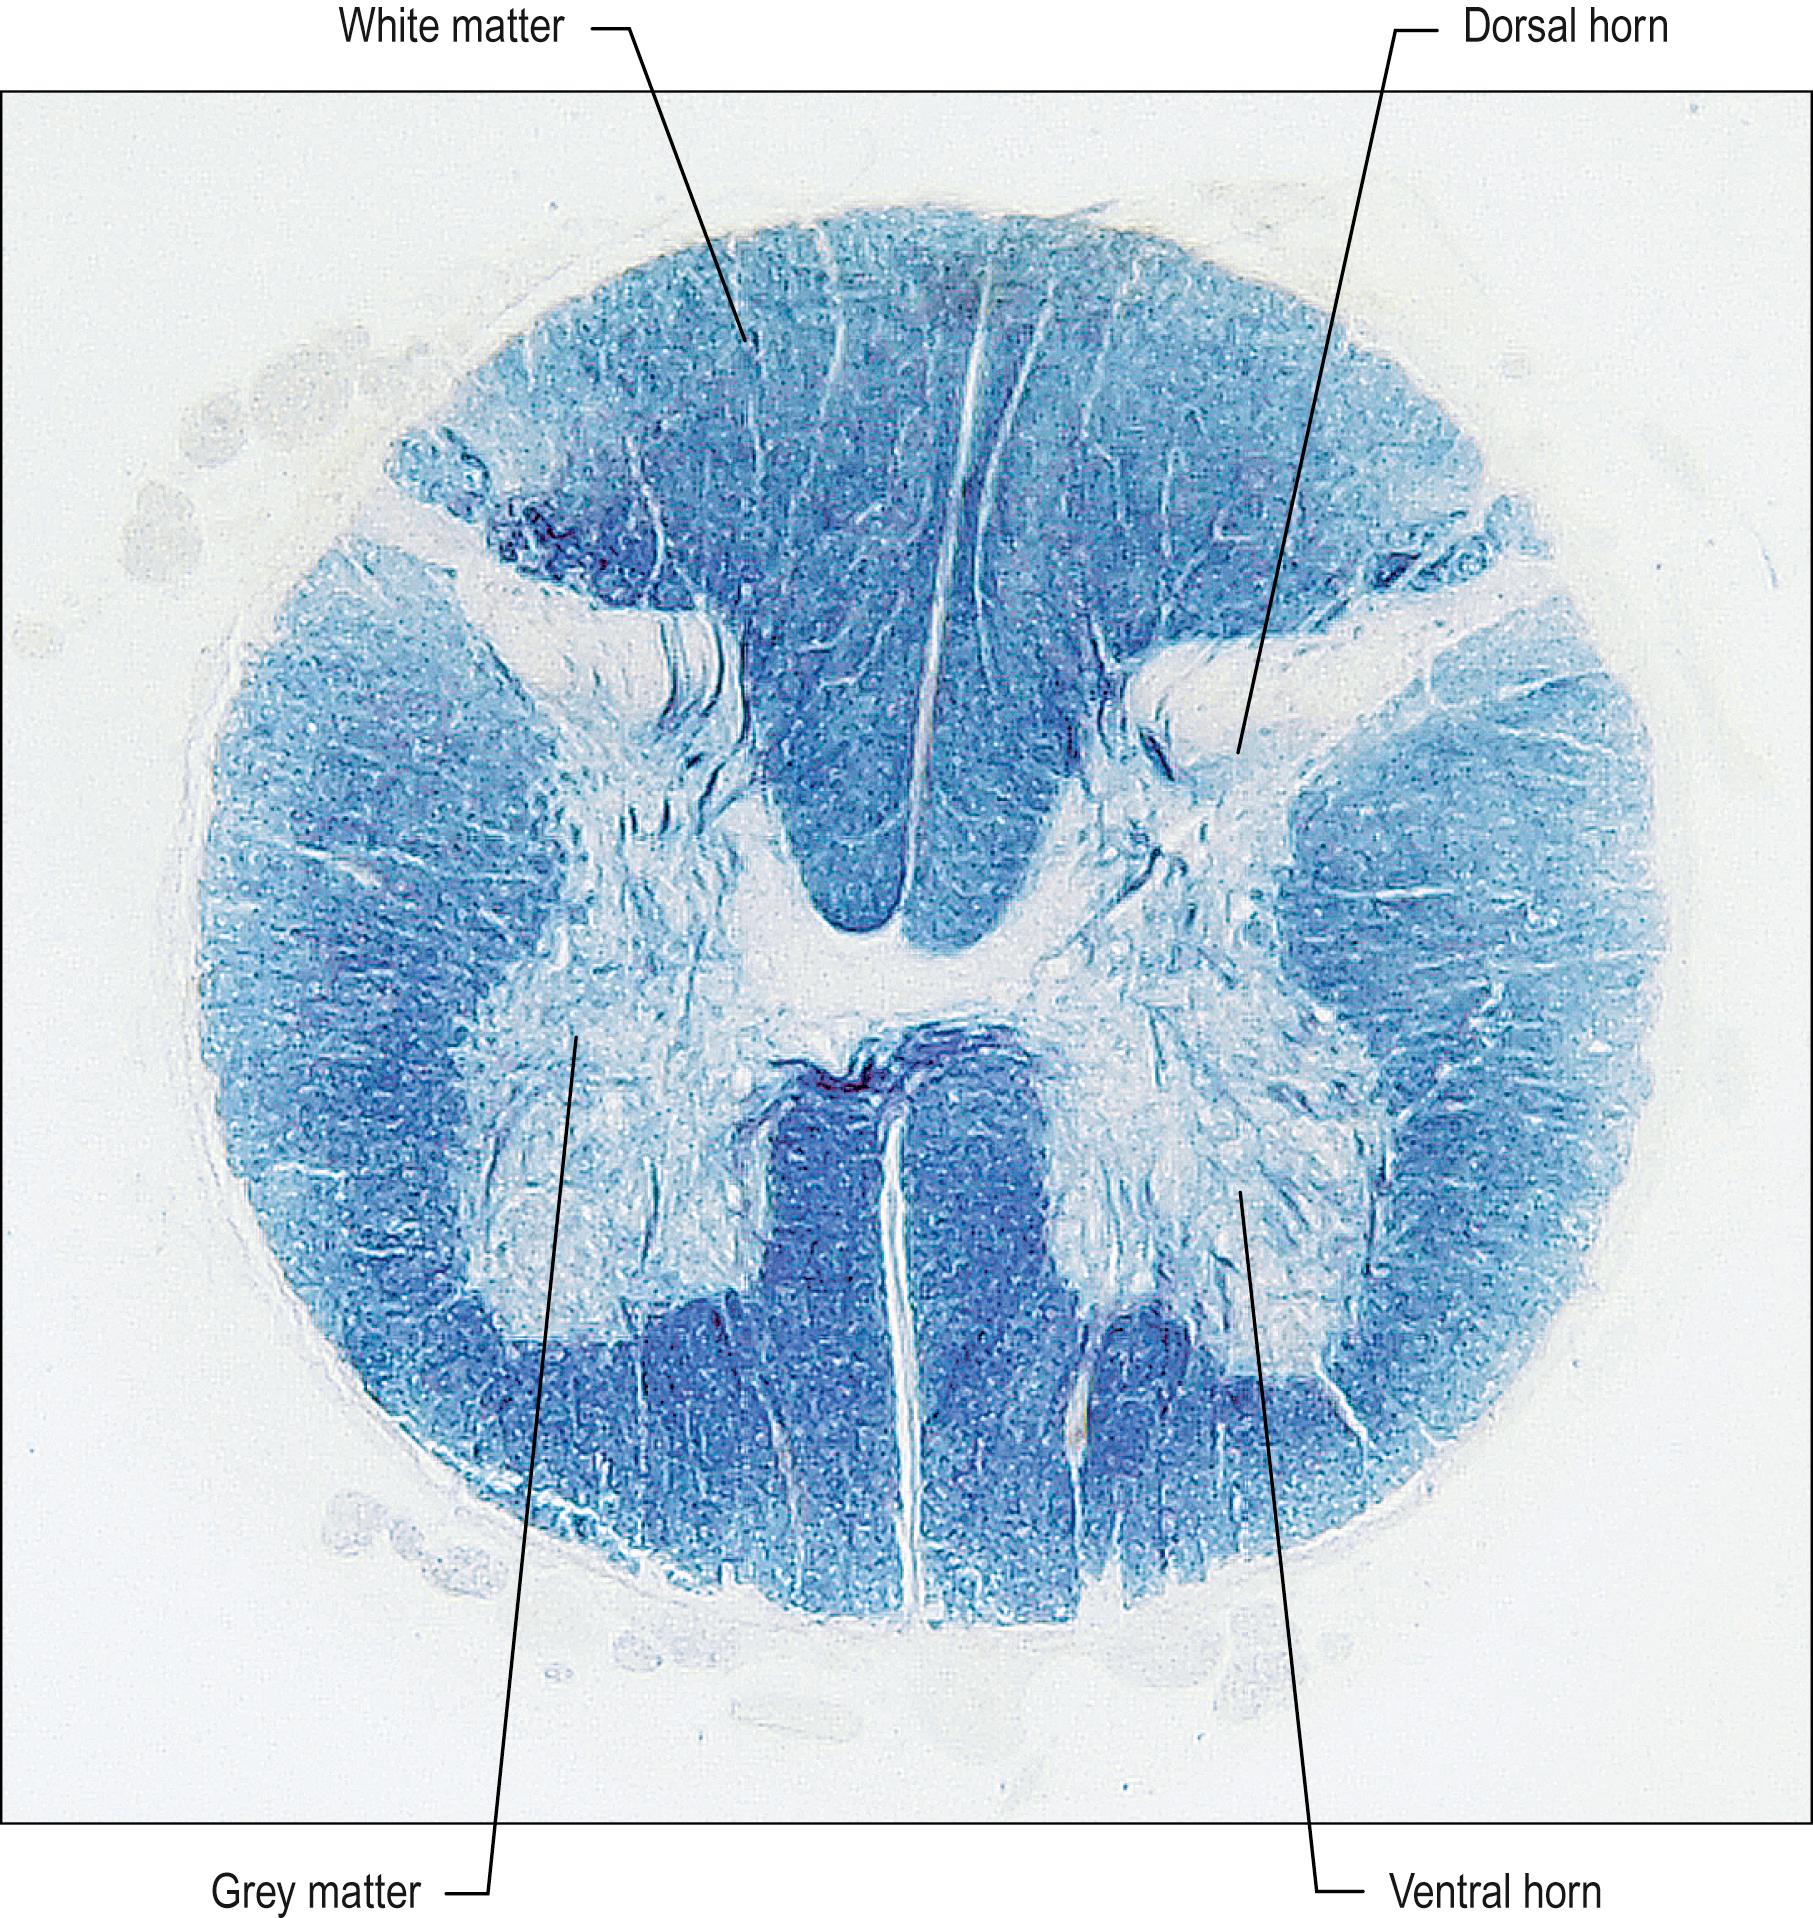

Fig. 24.2, A transverse section through the spinal cord, illustrating the disposition of grey and white matter and the attachment of dorsal and ventral spinal nerve roots.

Internally, the spinal cord consists of a central core of grey matter surrounded by white matter. The grey matter is configured in a characteristic H, or butterfly, shape that has projections known as dorsal (posterior) and ventral (anterior) horns ( Fig. 24.3 ). In general, neurones situated in the dorsal horn are primarily concerned with sensory functions whilst those in the ventral horn are mostly associated with motor activities. At thoracic and upper lumbar levels of the spinal cord a small lateral horn is additionally present, marking the location of the cell bodies of preganglionic sympathetic neurones. The central canal, a vestigial component of the ventricular system, lies at the centre of the spinal grey matter and runs the length of the cord. The white matter of the spinal cord consists of ascending and descending tracts that link spinal cord segments to one another and the spinal cord to the brain.

Fig. 24.3, A transverse section through the spinal cord at lumbar level. The section has been stained for nerve fibres, leaving the grey matter relatively unstained.